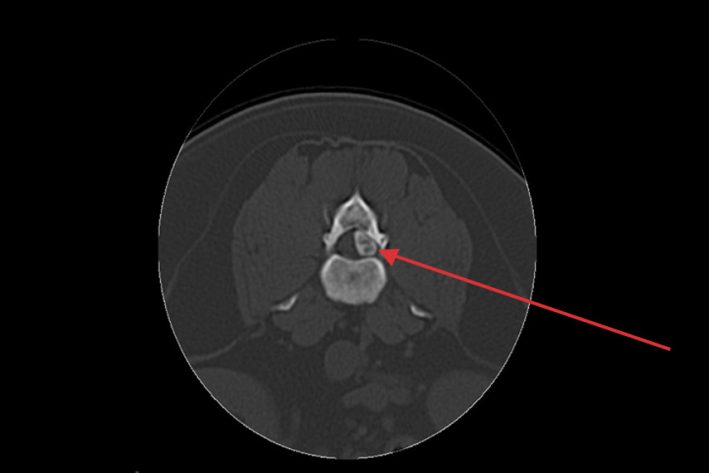

Rückenmarkstumor (Meningeom)

Rückenmarkstumor (Meningeom). Am Übergang der Brust- zur Lendenwirbelsäule

CT 3D-Rektonstruktion nach Laminektomie und Entfernung des Rückenmarkstumors